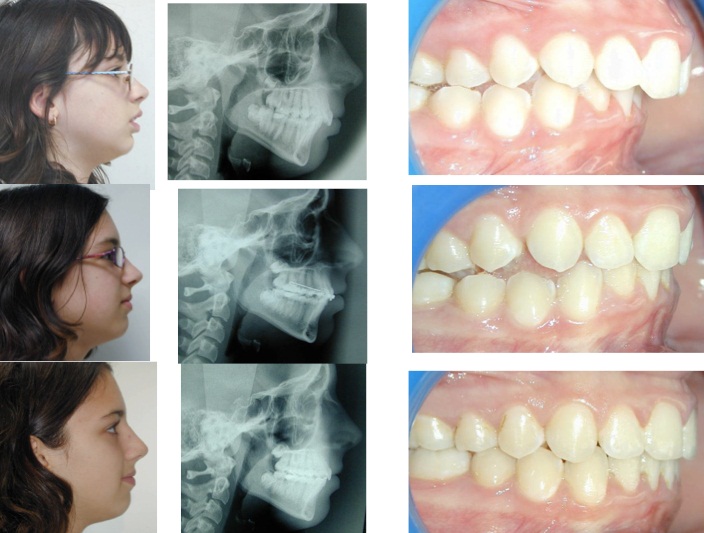

ორთოდონტიაში ფოტოგრაფია უბრალოდ აუცილებელია მკურნალობის პროცესის მიმდინარეობისა და საბოლოო შედეგის შესაფასებლად. ამასთან საჭიროა არამარტო პირშიგნითა, არამედ პირგარეთა ფოტოების ანალიზიც.